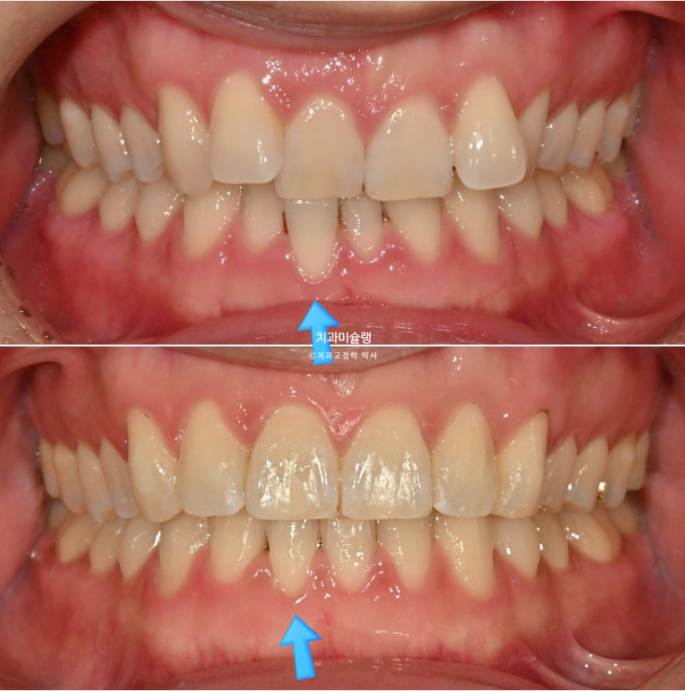

앞니 높낮이가 맞아지면 들쑥날쑥 했던 잇몸라인은 자연스럽게 맞아집니다.

이제 전후 비교 보겠습니다.

중심선 불일치는 부분교정의 한계점으로 그대로 덧니를 포함한 배열만은 완벽합니다.

특히 아래 앞니 중 튀어나와있던 파란 화살표 앞니는 배열 과정에서 잇몸라인도 자연스럽게 주변과 맞아집니다.